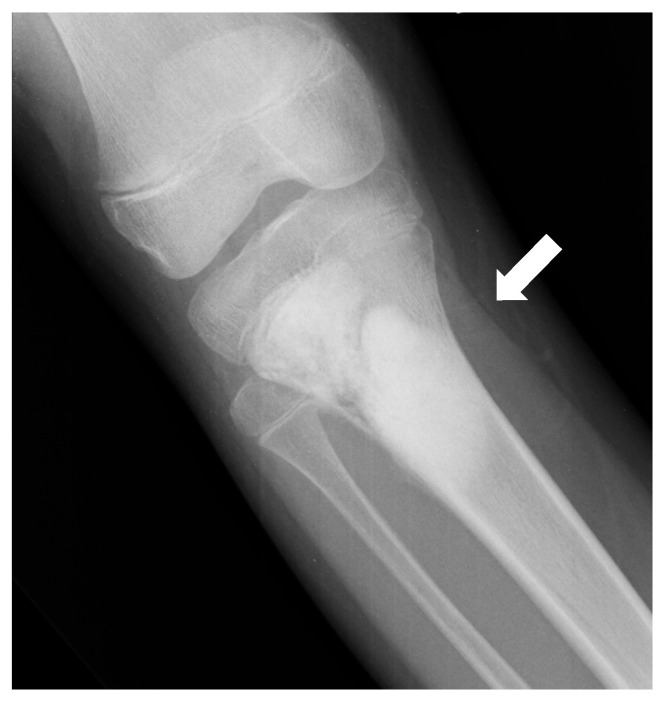

Estudios de imagen

- Patrón de destrucción: Puede mostrar destrucción medular y cortical. Bordes generalmente borrosos, con amplia zona de transición. El tipo de destrucción puede ser moteado o permeativo, raramente geográfico.

- Matriz tumoral: El grado de radiopacidad refleja la cantidad de producción ósea tumoral. Pueden aparecer como lesiones esclerosas puras, osteolíticas puras o, más frecuentemente, mixtas.

- Reacción perióstica: Puede adoptar forma de "sol naciente" (sunburst), "púas de peine", triángulo de Codman y, menos frecuentemente, laminar en "hojas de cebolla".

- Masa de partes blandas: Frecuente, con focos de esclerosis.